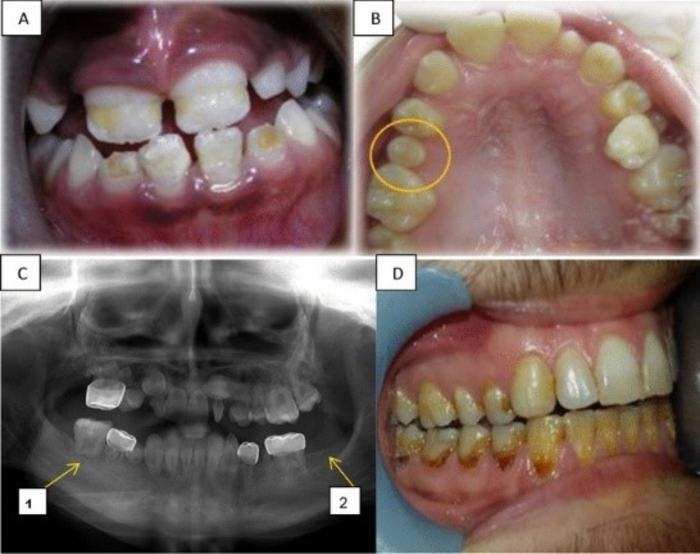

IMAGE: LONG TERM DENTAL EFFECTS. (A) HYPOPLASIA IN THE FRONT UPPER AND LOWER TEETH OF A GIRL AGED 9 YEARS, TREATED FOR ALL AT AGE 3.5 YEARS. (B) MICRODONTIA SHOWING THE SECOND UPPER RIGHT PREMOLAR IN A GIRL OF12 YEARS, TREATED FOR NEUROBLASTOMA AT AGE 4 YEARS. (C) A PANORAMIC RADIOGRAPH OF A 12-YEAR-OLD BOY DIAGNOSED WITH BURKITT'S LYMPHOMA AT AGE 4 YEARS, REVEALING: C1. ALTERED ROOT DEVELOPMENT AT THE FIRST LOWER RIGHT MOLAR, C2. HYPODONTIA OF THE SECOND LOWER LEFT MOLAR. (D) RADIATION CARIES IN A 21-YEAR-OLD BOY TREATED FOR NEUROECTODERMAL TUMOR AT AGE 14 YEARS. view more

CREDIT: ELINOR HALPERSON_HEBREW UNIVERSITY

Abnormalities included missing or small teeth, root development and enamel structure damage, over-retention of primary teeth; impaction; premature eruption; decreased temporomandibular joint (TMJ) mobility; inability to open the mouth or jaw and facial deformities.